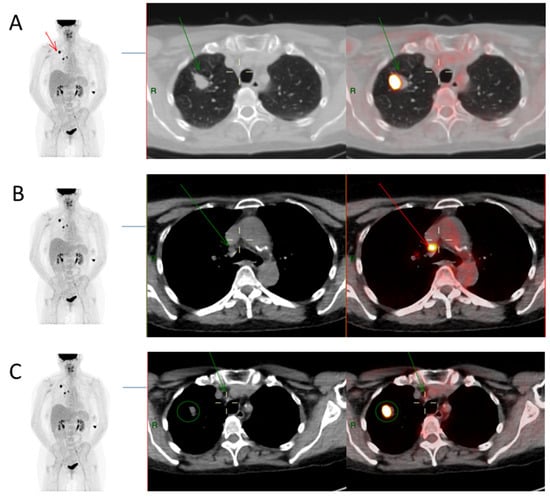

As an illustration, FDG PET/CT images from case #52 are presented to show the primary lesion as well as positive and negative mediastinal lymph nodes in Figure 1, which includes details of the SUVmax values along with the calculation carried out to determine the various SUVmax-derived ratios.

Figure 1.

Extracted images from FDG PET/CT scan of a single patient (Case #52). (A) Primary tumour—FDG PET/CT images showing a right upper lobe tumour (red arrow in image on left and green arrow in Axial CT and fused PET/CT images) with measured SUVmax value of 26.1. SUVmax was also obtained from reference background structures: mediastinal blood pool (ascending aorta), SUVmax 2.9; and liver (right lobe), SUVmax 4.5. (B) Positive mediastinal lymph node on histology—SUVmax of mediastinal nodal station 4R (7 mm right lower paratracheal node, green arrow) was 8.0, hence SUV ratios of MR (8/2.9 = 2.8), LR (8/4.5 = 1.8), TR (8/26.1 = 0.3), and SR (8/7 = 1.1). 4R nodal pathology was confirmed to be metastatic. (C) the 4 mm mediastinal nodal station 2R (4 mm right upper paratracheal node, green arrow) has SUVmax value of 2.5, giving SUV ratios of MR (2.5/2.9 = 0.9), LR (2.5/4.5 = 0.6), TR (2.5/26.1 = 0.1), and SR (2.5/4 = 0.6). The 2R nodal pathology was benign. The primary tumour is illustrated by green circle in this image.